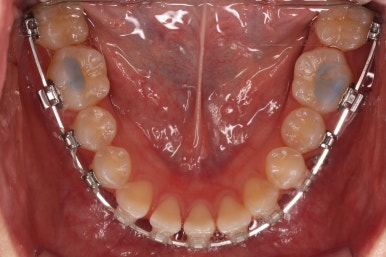

부산교정 키다리아저씨치과에서 결손치아 부분을 임플란트 하지 않고 치아교정을 통해서 개선한 이번 환자분의 치료를 마무리한 사진입니다.

치열은 가지런해졌고, 틈새는 없이 마무리되었습니다. 아랫니가 3개이지만 마치 4개인 것처럼 마무리하였고, 따라서 위~아래 치열의 중앙도 거의 맞게 마무리하였습니다.

(한 쪽은 송곳니를 앞니 대신 사용해야 했어서 크기 문제로 완벽히는 중앙을 맞추기 힘듭니다.)